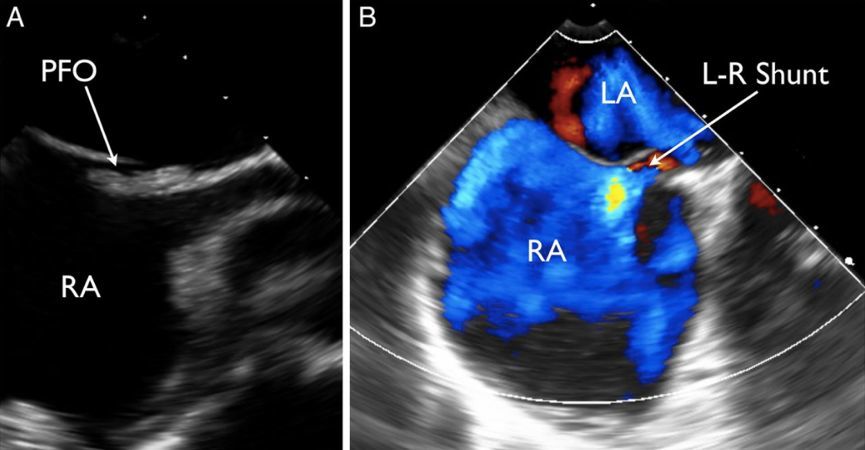

列位看官,你们肯定忽视了一种心脏疾病所致的偏头痛:卵圆孔未闭。

卵圆孔其实是心房原发隔与继发隔之间的一个缝隙。由于这个解剖结构的存在,当情绪激动等其他原因导致胸腔内压力过高时,可能会导致心房之间出现右向左的分流。因静脉血中化学物质如 5-羟色胺等血管活性物质较多,在分流后会导致脑血管扩张出现偏头痛。

所以在临床中会有一些不明原因偏头痛的患者,能够卵圆孔未闭封堵中获益。

卵圆孔未闭,一般是左向右分流,在右心压力升高时,可出现右向左分流

卵圆孔处的骑跨血栓

除功能性头痛,卵圆孔未闭更大的潜在风险,是导致矛盾栓塞。即来自下肢深静脉或右心系统的血栓,通过卵圆孔进入左心系统,继而导致外周动脉尤其是脑血管栓塞。